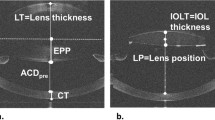

We imaged anterior segments with CASIA2 (TOMEY Corporation, Nagoya, Japan) preoperatively and at one month after surgery. The CASIA2 device, an AS–OCT device with a swept-source laser wavelength of 1310 nm, can measure depths as large as the anterior segment length, and is useful for the evaluation of the crystalline lens shape and actual postoperative IOL position. The CASIA2 software loads the image (shape) and corrects it based on a fixed refractive index at each segment. For preoperative anterior segment data, the corneal ACR, the PCR, CT, and LT were determined. The ATA depth was determined as the perpendicular distance between the posterior corneal surface and the intersection point of a line that joined the angle recesses on the cross-sectional horizontal image and the corneal vertex. The ASD for the crystalline lens was automatically calculated as the distance between the anterior surface of the lens and the posterior surface of the cornea. In addition, the PSD for the crystalline lens was calculated by adding the automatically calculated LT value to the ASD. The equatorial surface for the crystalline lens was determined by drawing a line through the intersection point of the anterior and the posterior curvature radii of the crystalline lens (i.e., the predicted equatorial surface). Additionally, the distance between the equatorial and the posterior surfaces of the cornea were quantitatively determined as the ESD of the crystalline lens. The anterior and posterior curvature radii of the crystalline lens were automatically traced to fit a circle with CASIA2 and were subsequently quantified (Fig. 5).

For the postoperative AS data, the anteriorly implanted IOL surface position was calculated as its distance from the posterior corneal surface (Fig. 5). If the crystalline lens axis was not identical to the optical axis, a straight-line distance was determined with the use of the crystalline lens axis.